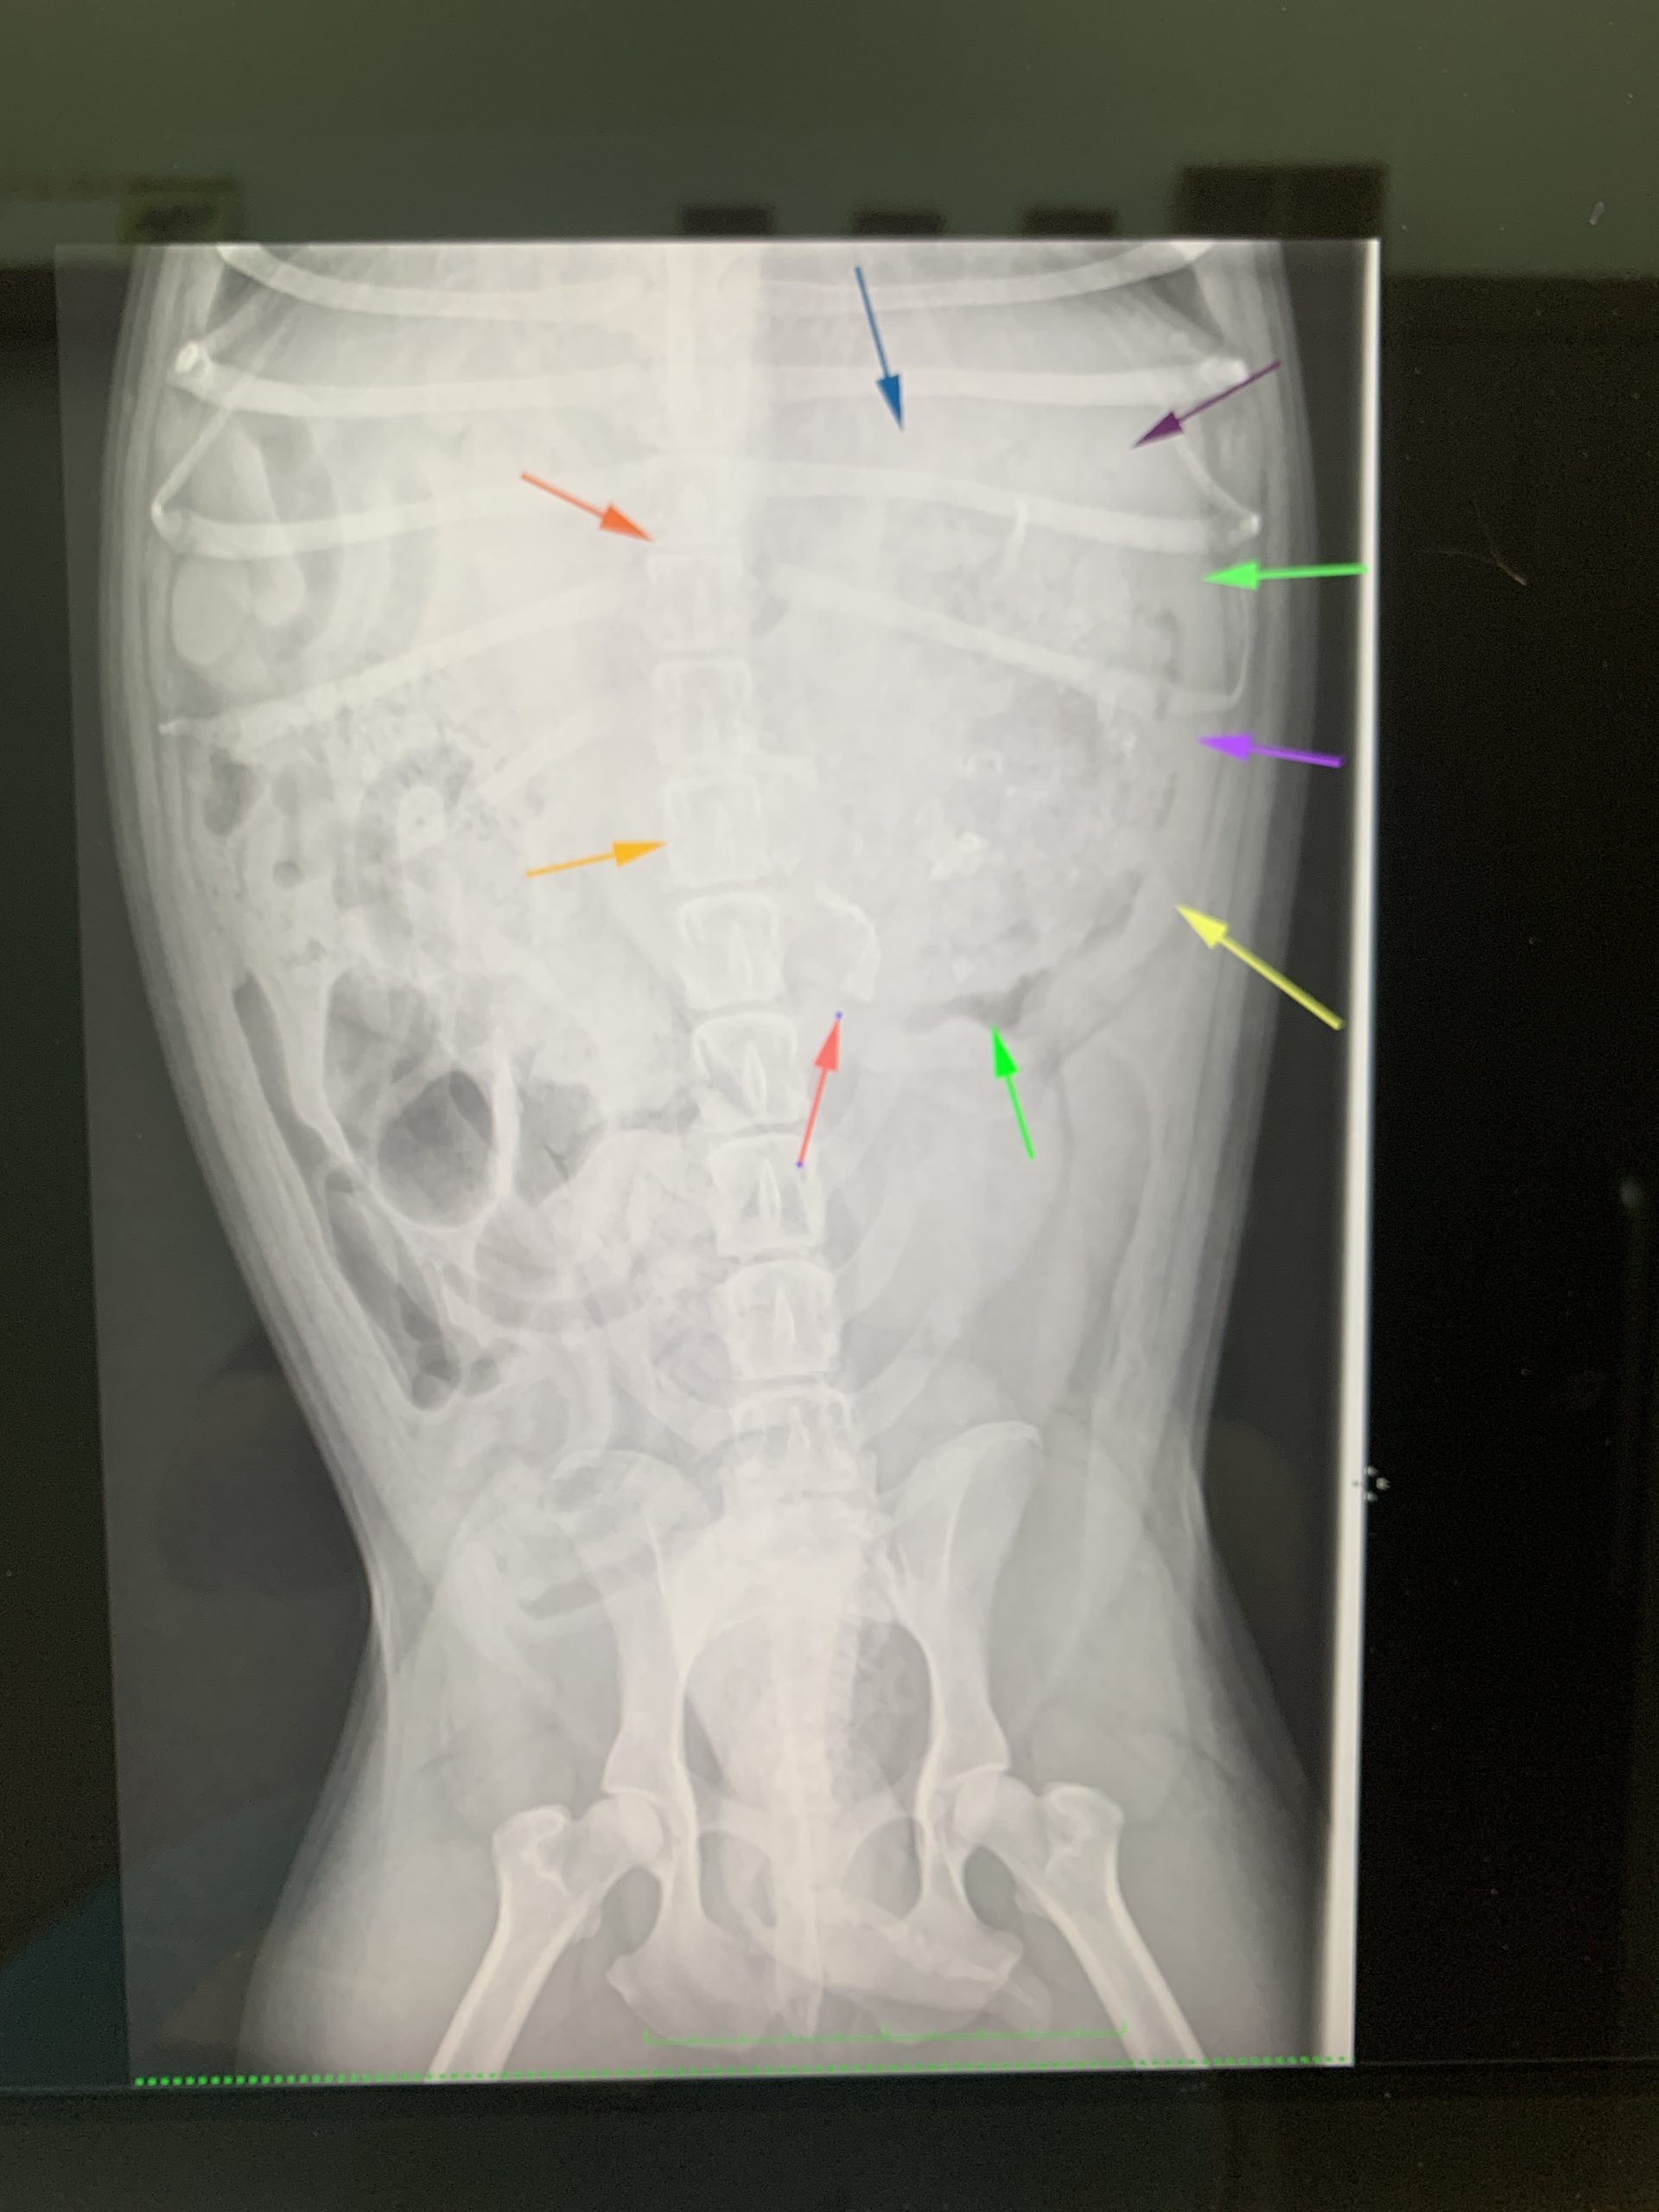

今回紹介する子は慢性的な嘔吐がありエコー検査では胃の粘膜が重度に腫れていたというものです。胃内に食事などが含まれる場合は構造が似ていれば異物か食事かを判断するのは困難になります。(棒やボールなどは構造がくっきりするのでエコー検査だけでも判断がつく場合があります。)今回もエコー検査だけでは胃の構造異常だけでレントゲン検査にて何か大きな構造物が判断しました。(矢印の部分が胃に当たります)